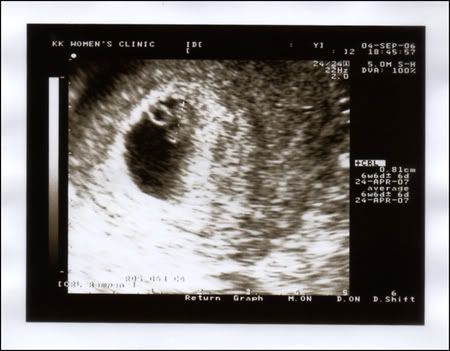

U guys dunno how much i wanted to shout out abt the news earlier.. but i tot i should wait till the babe's more stable... coz when we first went to see the gynae at supposedly 6-7wks, the gynae couldn't see the babe in the gestational sac... we were told to see him again a wk later to see how it was progressing and i'm telling ya, it was the longest 1wk wait ever!!!

but al-hamdulillah, 1wk later, we got to see our babe!!...

imagine how happy we new parents-to-be to see this being formed and seeing the rapid heartbeat beating!!.... aaaah..... i couldn't believe that i was excited coz i was the one who's soooo sceptical of starting a family in the first place!....

and so, at 11wks, we went to see our new gynae who's pretty quirky, straight to the point and a play-safe one... coz he told us SEX is a no-no!... where got such thing one??!.... but niways, again, we got to see our babe...

it's tripled in length now and the EDD's expected to be 20 Apr!... yeay!!... a day after my bro's bday, a week before the Daddy's bday!!... tat'll be my present to the both of them next year!.. ahhahhaa.... ;)

So that's our babe at 16wks... the due date has been postponed to 22 Apr instead of 20 Apr but somehow, i'd like to think that the babe will wanna pop out on the 20th coz i'd prefer an Aries babe than a semi-Aries cum Tauras babe!.. hehehehe...

but anyways, when scanned, it's hands and legs were up in the air.. occasionally, it bumped around as if on an imaginary trampoline!... how cute!!... it actually brought a tear to my eye!.. ahhahaa.... oooooh!!!... and the doc guessed the gender!.... it's not so clear yet.. so i'll not release the gender as yet till it's confirmed.. yah.. in case some of u may be wondering - we didn't wanna know the gender of the babe.. but the doc seemed adamant to tell us... we do wonder y!... so we told him that if in any case, the babe wants us to know, and he can confirm the gender, then tell us.. if not, we can juz be surprised later!.. ;)

oh!... and i'm sooooo blardy excited!!... coz the doc said that he'll give us a 4-D scan of the babe in due course.. prolly after the detailed scan... so hopefully, he stick to his promise and let us see the babe's face in advance!!.... i soooooo can't freakin wait!!!!.....

anyways, my last visit to the gynae 2days ago, the gynae wanted to check it's neck's strength or something... but the babe wouldn't cooperate coz it's in a weird position... but everything else, acc to the gynae looked OK... the babe looked stable oredi.. the heartbeat's pumping like nobody's business... al-hamdulillah....

u see how the babe's end is up?... hmmm.... wonder wat it's doing??!!.... kwang.. kwang.. kwang.. anyways, one of the better news of the day is, i'm not really gaining weight!!... yeay!!!.... ;) i've only gained, at most 2kg over the past 3mths!.. yippee!!.... but must say lah... Rosma's question was intriguing - so where did all these babats come from eh?!... hahahhaha.... coz my tummy do look like one large tumour!!.... ;( the peeps in the office dun seem to notice (coz i'm still wearing my normal office wear), but i think they may have known oredi coz i got one lousy secret-keeper boss in the office!!.... baaaahh!!....

i was supposed to do the 3D scan of my babe yest... but, the doc said that the babe's not in the right position to do it... so.. haiiizzz... have to wait for another month.... and we found out that my placenta is pretty low... it's at the borderline and there's a slight chance that i may not be able to deliver normally... :( so now, i'm hoping and praying that the placenta will go up in the the nx few mths so that i've got a good chance of having a normal delivery!....